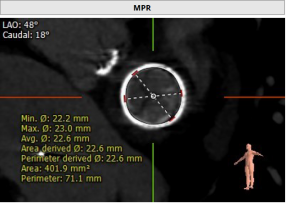

CT评估:既往植入佰仁生物瓣,25#,True ID 23mm, 高度17mm,房间隔穿刺高度约为25.6mm, 模拟植入23mm SAPIEN 3后,Neo-LVOT 153.7mm2 小于170 mm2,aorta-mitral 平面角度125.9°,mitral-septum distance 3mm,有流出道狭窄风险。CT推荐角度为RAO 40°,房间隔无明显钙化、膨出,房间隔长度可满足穿刺需要。拟植入SAPIEN 3 23mmPLUS3ml。